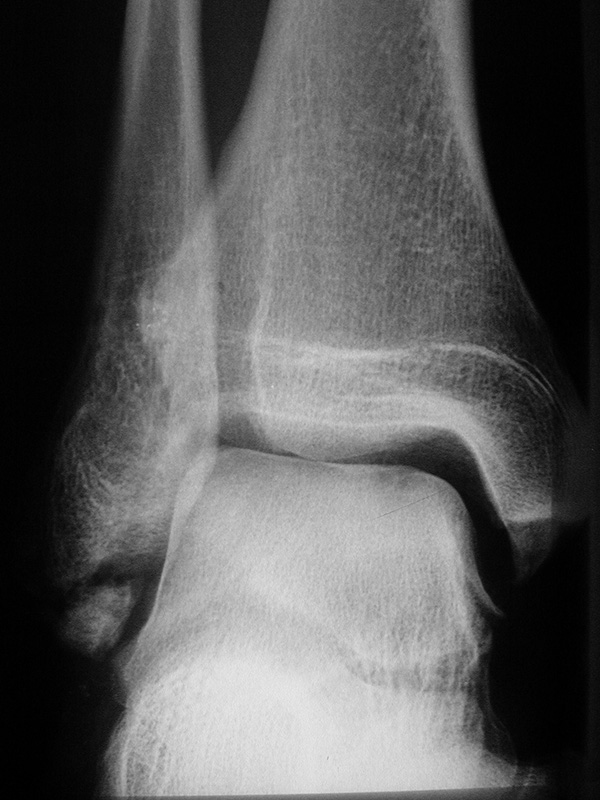

Stressaufnahme des oberen Sprunggelenks lateral

Position:

• Patient in Seitenlage auf dem Röntgentisch, zu untersuchender Fuß unten und seitlich auf der Röntgenkassette liegend (Achse des Fußes parallel zum Zentralstrahl).

• Zentralstrahl mittig auf das obere Sprunggelenk fokussiert.

• Film horizontal auf dem Röntgentisch.

• Röntgenröhre 0° vertikal.

• Der Fuß liegt in der Haltevorrichtung (z.B. Telos-Gerät, Scheuba-Apparat). Die Ferse wird von dorsal stabilisiert.

• Von ventral wird über die Tibia ein kontrollierter Druck von bis zu 15 daN (Dekanewton, entspricht ca. 15 kg) aufgebaut.

Kennzeichen des Röntgenbildes:

• Laterale Abbildung des oberen Sprunggelenks.

• Beurteilung der Translokation des Talus nach ventral (Talusvorschub).

• Gemessen wird die Verschiebung der Tibiaachse gegenüber der Talusachse.

• Als pathologisch gelten Talusvorschub > 2 mm im Seitenvergleich oder absoluter Talusvorschub > 4 mm.

Besondere Bemerkungen zum Beispielbild:

• Abbildung des oberen Sprunggelenks lateral.

• Fremdkörper in den plantaren Weichteilen in Höhe der plantaren Begrenzung des Kalkaneus.